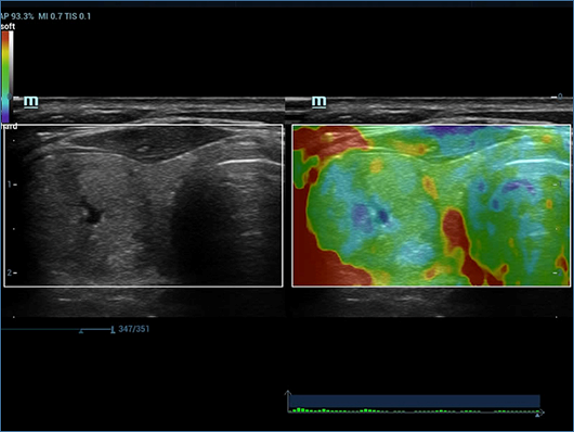

Mindray, ?irketin kuruldu?u gĂŒnden bu yana sĂŒrekli olarak tan?sal do?rulu?u iyile?tirmeye ?al??maktad?r. Devrim niteli?indeki ZONE Sonography? Teknolojisi ile desteklenen Resona 7ânin yeni ZST+ platformu, b?lge g?rĂŒntĂŒsĂŒ alma ve kanal veri i?leme ?zellikleri ile ultrason g?rĂŒntĂŒsĂŒ kalitesini daha ĂŒst bir dĂŒzeye ??kar?yor.

Resona 7, ĂŒstĂŒn dĂŒzeyde g?rĂŒntĂŒ kalitesine ek olarak, vaskĂŒler hemodinamik de?erlendirmesi i?in devrim niteli?indeki V Ak??? ile fetĂŒs CNS tan?lamas? i?in 3 boyutlu veri kĂŒmesinden dĂŒzlem g?rĂŒntĂŒsĂŒ alma konusunda en iyi birime sahip oldu?undan, klinik ara?t?rma yeterliklerini de art?rmaktad?r. En sezgisel, harekete dayal? ?oklu dokunmatik i?letim ile tĂŒm temel klinik ?zellikleri bir araya getiren Resona 7, ultrason yenili?i konusunda ger?ek anlamda yeni dalgalara ?ncĂŒlĂŒk ediyor.